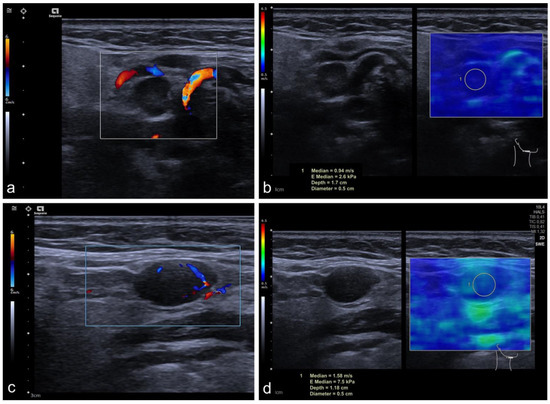

2.2. Imaging Protocol

2.3. Perfusion Analysis